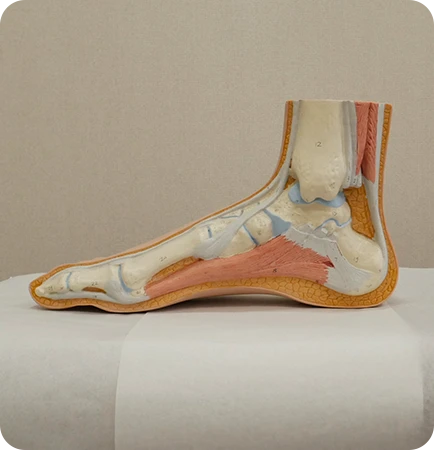

발 모양에 따라

▲ 평발

▲ 요족

▲ 정상발

평발형 오다리

요족형 오다리

평발형 엑스다리

요족형 엑스다리

X다리 일 때,

평발인 경우가 많음

휜다리는 발과 다리의 교정뿐 만아니라 골반과 척추의 밸런스를 맞춰야하는데 이때 가장 필요한 것이 족부 교정입니다.

발과 발목의 변형을 교정할 필요가 없는 휜다리는 흔치 않으며 발을 교정해야 교정후 재발 걱정이 없습니다.